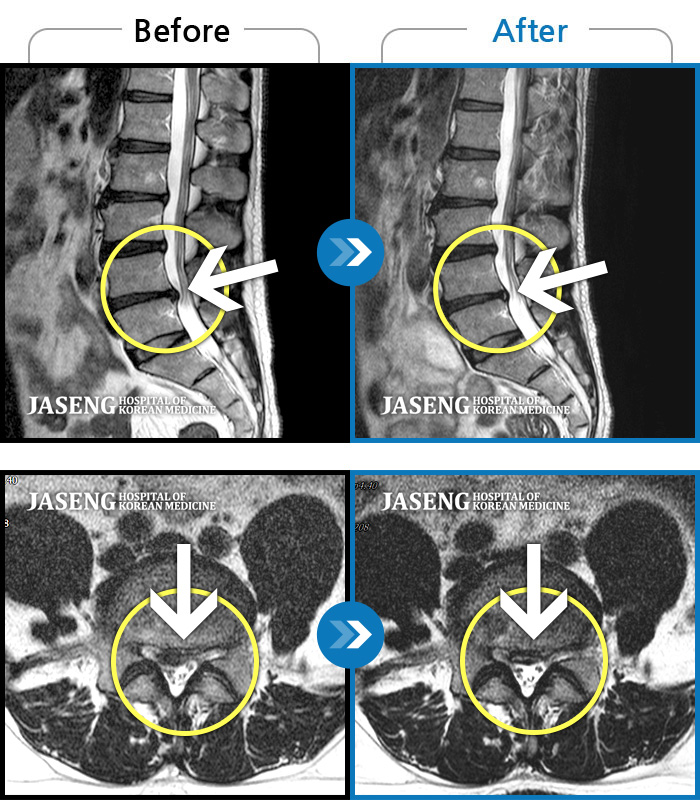

ȯںп Ǹ ǿ ԿǾ, ο ġ ۿ Ƿ ġḦ Ͻñ ٶϴ.